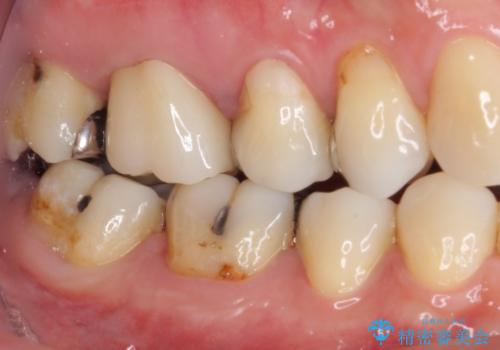

- 上の奥歯に咬んだときの痛みを感じて来院された患者様です。

まずは根管治療を行い、その後フルジルコニアクラウンにて補綴することとしました。

根管治療後には痛みが引き、半年後のレントゲンからは根尖部の病変が縮小している様子が分かりました。

咬んだときの感触も良好で、患者様には大変満足していただきました。